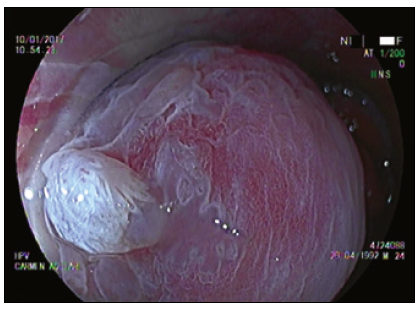

Cromoendoscopía digestiva magnificada en sustitución de la AAR convencional

La AAR en la literatura actual es sinónimo de colposcopía anal con tinción química.5, 7, 17, 18 Utilizando las nuevas tecnologías de la videoendoscopía digestiva es posible alcanzar una magnificación óptica de 200x, significativamente superior a la de un colposcopio de última generación. Nosotros trabajamos con una imagen magnificada de 100x que nos permite un mejor manejo del foco (Figuras 1 y 2).

El uso de capuchón es necesario al comienzo del entrenamiento. Con el advenimiento del sistema Laséreo, hemos sustituído la acetotinción por la cromotinción electrónica. Esto ha simplificado la técnica, acortando los plazos y las rotaciones del anoscopio, que pueden resultar molestas especialmente cuando hay hemorroides. El destaque de los cambios en el patrón vascular y glandular es igual de efectivo (Figura 3). El uso del colonoscopio permite valorar el recto, más allá del canal anal, con el fin de diagnosticar las metaplasias escamosas que pueden ser asiento de displasias VPH (Figura 4).